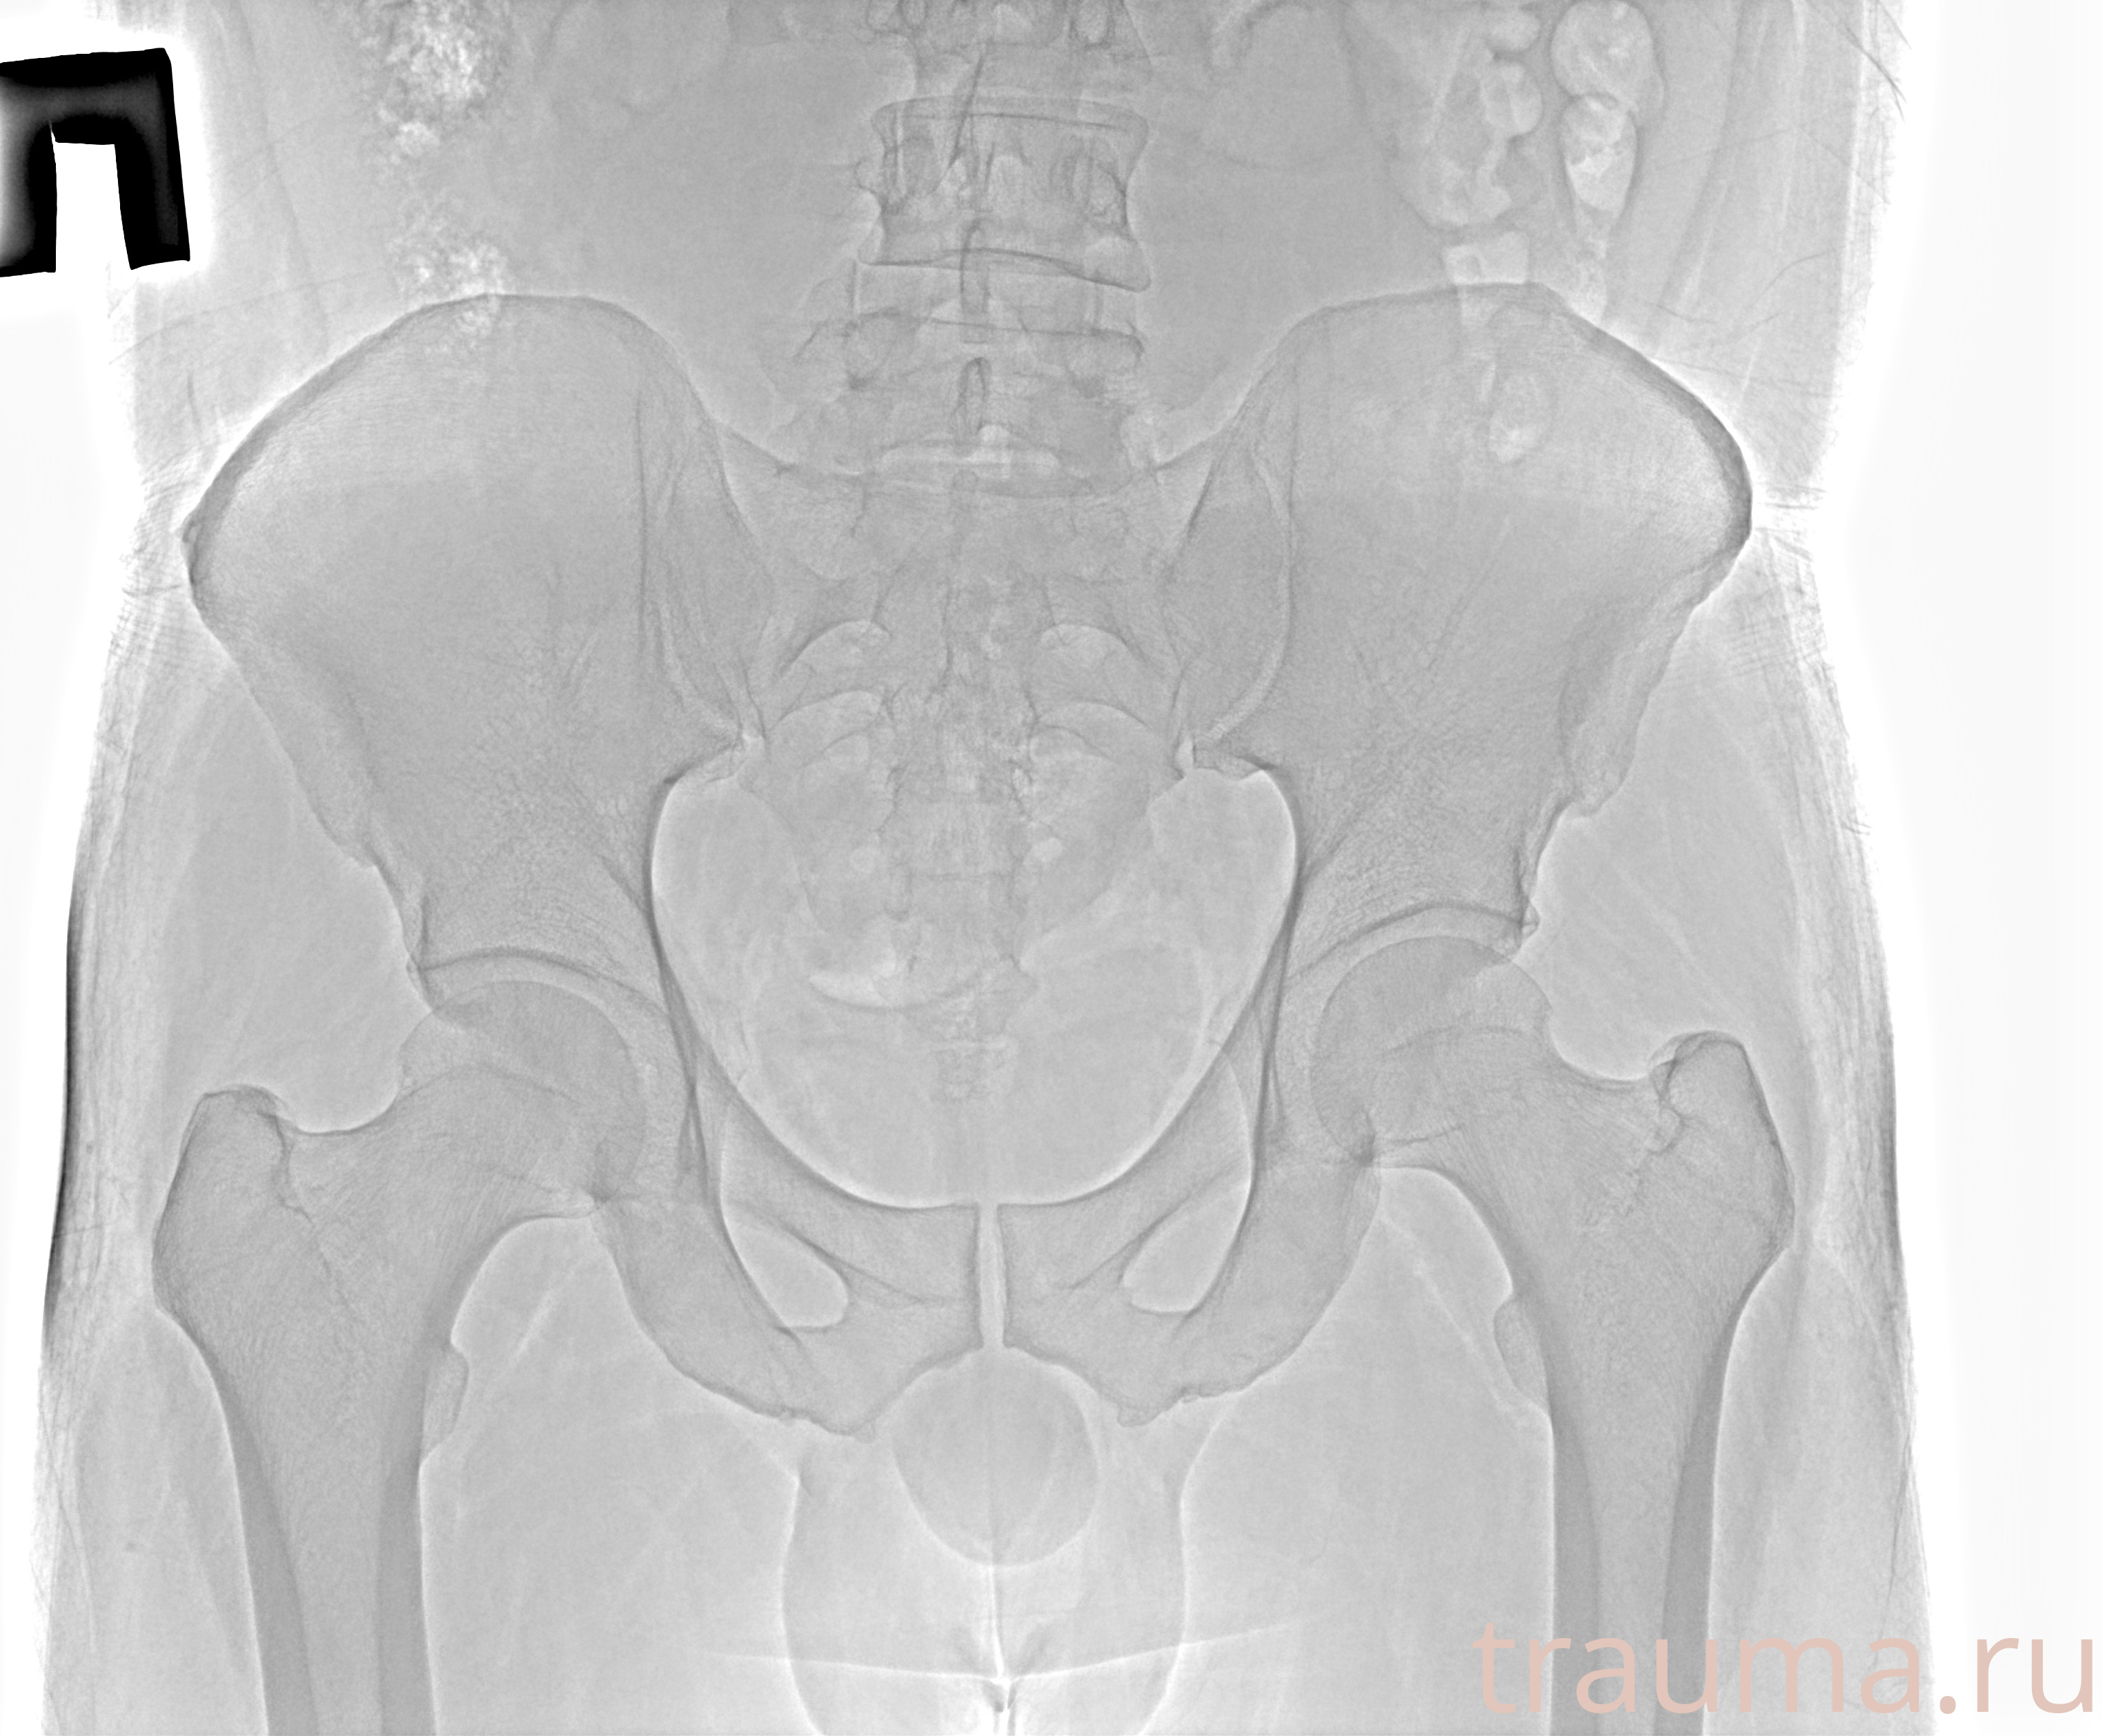

Рентгенограммы

Рентген на дому: по вашему адресу приезжает врач-рентгенолог, травматолог-ортопед с мобильным рентгеновским аппаратом, проводит диагностику травмы или заболевания, делает необходимые рентгенограммы, дает рекомендации по дальнейшему лечению. Получить качественные снимки в домашних условиях возможно благодаря уникальной методике, разработанной МосРентген Центром для института  Склифосовского